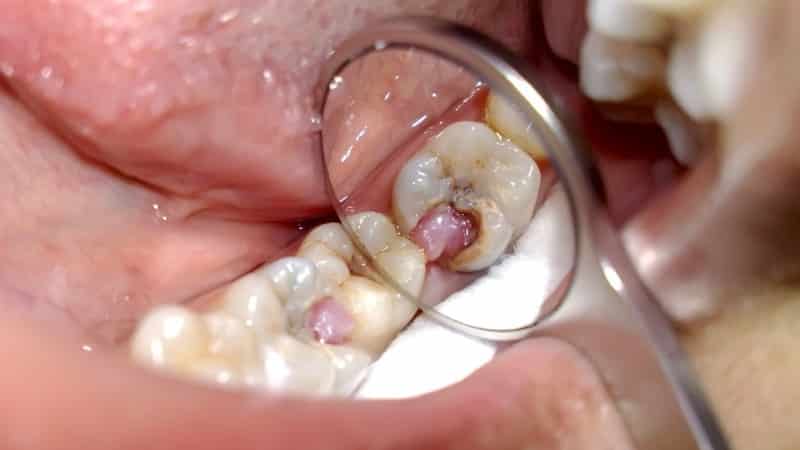

При кариесе происходит разрушение эмали и дентина, а также активное размножение болезнетворных микроорганизмов. Глубокое поражение может затрагивать пульпу с нервными окончаниями, что вызывает болевые ощущения. После устранения источника боли она, как правило, исчезает.

Кариозные осложнения связаны с повреждением пульпы и развитием воспалительного процесса, затрагивающего нервные окончания. В таких случаях боль может возникать без видимых причин. Одним из серьезных осложнений является не вылеченный пульпит, который может привести к воспалению в челюстной кости и надкостнице, а также к образованию флюса.